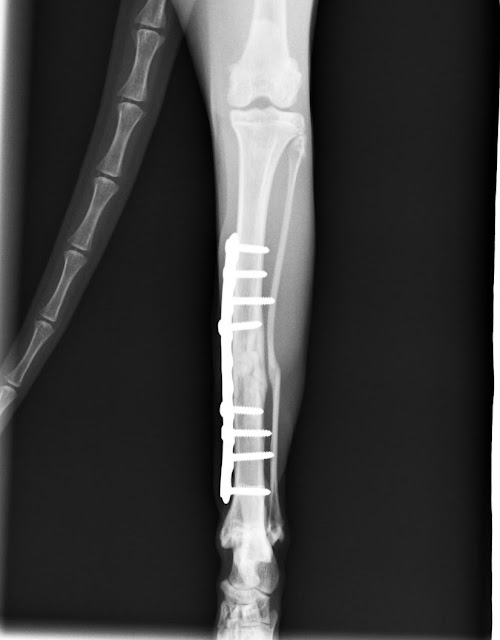

8 Weeks Post-Op - lots of new bone formation!

So the 8 week xrays show good new bone formation and he has the go ahead to start his 'gradual return to normal activities'... which I labelled GR2F (Gradual Return to Freedom). The vets wanted him to have 15 - 20 minutes loose a couple of times a day, and for this program to gradually increase over 2 - 4 weeks. For the first few days, he got a couple of hours loose, in the morning and then after work in the evening. He was cautious with stairs and jumping, very smart of him, such a good boy. He ran though, on the flat, thrilled to not be tied down. Aska was very happy to have someone join in on the chase, as the old aunties aren't really into that anymore and she was tired of doing all the running alone. Which she did anyway, because a young cat needs to, but it is so much more fun with a partner in crime, you know.

And that effort has paid off. A week and a half ago, he had the 8 weeks post-op xrays to see how his leg was healing. My vet and the surgeon were both very pleased with how well the bone has healed. Andi got the go-ahead to start having some free time loose in the house. I was cautioned that because he had spent two months with no exercise, he would have muscle wasting and would need to gradually build up his strength.